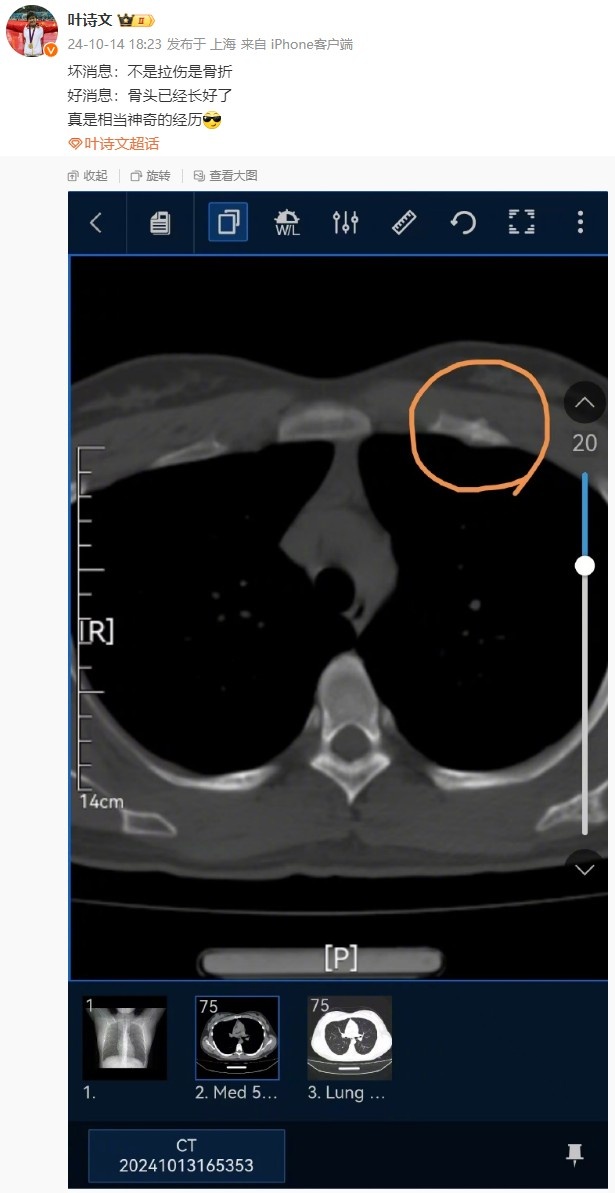

不过赛后,叶诗文透露,明天的女子100米蛙泳比赛她将选择退赛。而就在此前,她在个人社交媒体表示自己骨折受伤(目前已经没有太大问题)。